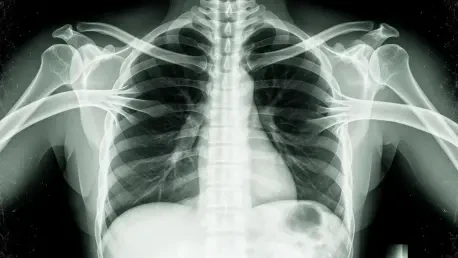

CliniciansaccustomedtotreatingX-raysasobjectiveanchorsinuncertaincasesaremeetingagenerativeAIfakethatlookseverybitrealonthefirstpassandstilldefieseasyverificationonthesecond. A peer-reviewed study found that text-to-image models can fabricate chest radiographs so anatomically plausible that radiologists flagged the forgeries correctly only 41% of the time when not warned of manipulation. Even after an alert, accuracy rose to roughly 75%, leaving a troubling gap. Automated screeners did not fare better; in several tests, the very model family that generated the images failed to tell real from synthetic. This collision of realism and ambiguity undermines long-standing habits: trusting pixel patterns, correlating with short clinical notes, and moving quickly in high-volume workflows. The stakes extend beyond misreads. Synthetic pathology can enable insurance scams, sway legal disputes, or poison training corpora, degrading future models in a self-reinforcing loop that blurs the line between signal and spoof.

What makes these images so compelling is not just high resolution but coherent anatomy under subtle constraints: rib spacing tracks patient size, cardiomediastinal contours stay proportionate, and text overlays, if any, mimic department styles. Simple artifact-spotting no longer suffices. Moreover, legacy protections in imaging pipelines were not built for this threat. DICOM headers can be edited, PACS archives mirror tampered files, and audit logs often track access rather than content integrity. Detector models trained on obvious compositing artifacts stumble on prompt-driven synthesis that bakes in realistic noise and equipment signatures. The result is a dual failure mode: humans over-trust context, while algorithms over-fit to stale tells. In triage settings, a forged pneumothorax can trigger unnecessary interventions; in oncology, a phantom lesion can reroute care plans. The cost is not hypothetical—it materializes wherever verification lags generation.